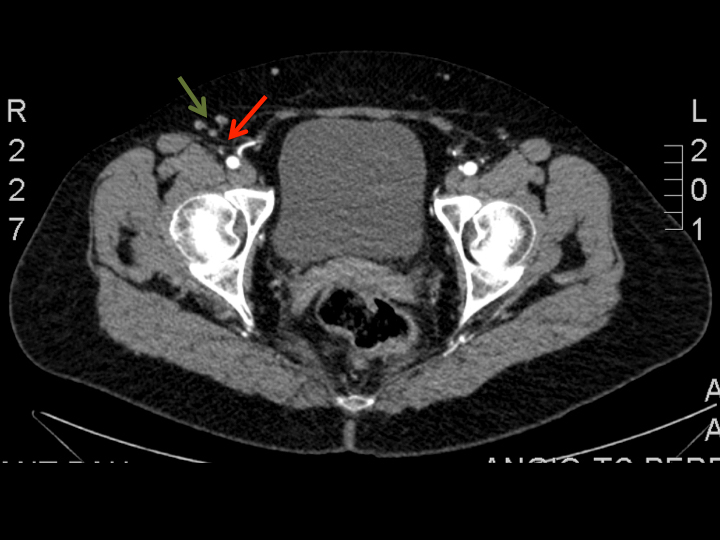

These nodes and their vascular pedicle are preoperatively assessed and precisely located using a combination of co-ordinates following computed tomography angiography (Figure 1).

Figure 1: Axial view of CT-angiography showing the right superficial inguinal lymph nodes (green arrows) and the nourishing superficial circumflex iliac vessels (red arrows). This helps to locate the lymph nodes to be harvested and its nourishing vessels, using a combination of coordinates in a system of cartesian axis.